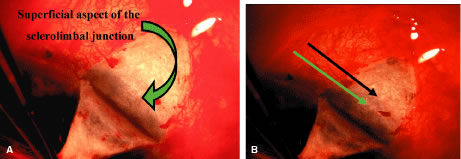

It is almost never appropriate to perform any surgical procedure other than an injection of retrobulbar alcohol or chlorpromazine or an enucleation or evisceration on a blind eye. Although the incidence of sympathetic ophthalmia is low, sympathetic ophthalmia is such a totally devastating complication that its potential occurrence mitigates against performing procedures that have the capacity to cause it. Sympathetic ophthalmia has been reported to occur with surgical peripheral iridectomy, filtration procedures of every kind, cyclocryotherapy, cyclophotocoagulation, and cyclodialysis. Retrobulbar alcohol tends to produce problems of its own, including numbness in the skull, ptosis, and strabismus. The experience with retrobulbar chlorpromazine is less extensive but promising because the pain relief it provides is usually excellent without production of the problems associated with retrobulbar alcohol. An injection of chlorpromazine, 25 mg, is placed in the retrobulbar space.

The most appropriate therapy for the blind, comfortable eye is no therapy. The most appropriate therapy for the eye that is blind and has moderate discomfort because of markedly fluctuating IOP is a long-acting agent such as slow-release timolol; once the pressure is stabilized, the timolol often may be stopped.

When patients learn that they have glaucoma, they may have an immediate decrease in the quality of life because of the anxiety that they experience as a result of knowing that they have a potentially blinding disease. Telling a patient that surgery may become necessary usually increases the degree of fear. Patients with glaucoma are often asymptomatic. The recommendation of surgery to prevent the loss of vision may be difficult for these patients to accept. They must have implicit trust in their surgeon. Their concerns are justified; surgery does not always work. Surgery does not always control the disease, and often it makes the vision worse. Consequently, fully informed consent must be obtained. The surgeon must be certain that the patient understands the risks of having surgery, the risks of not having surgery, the benefits of having surgery, and the benefits of not having surgery. In addition, the patient must be given a realistic idea of what to expect.

Back to Top